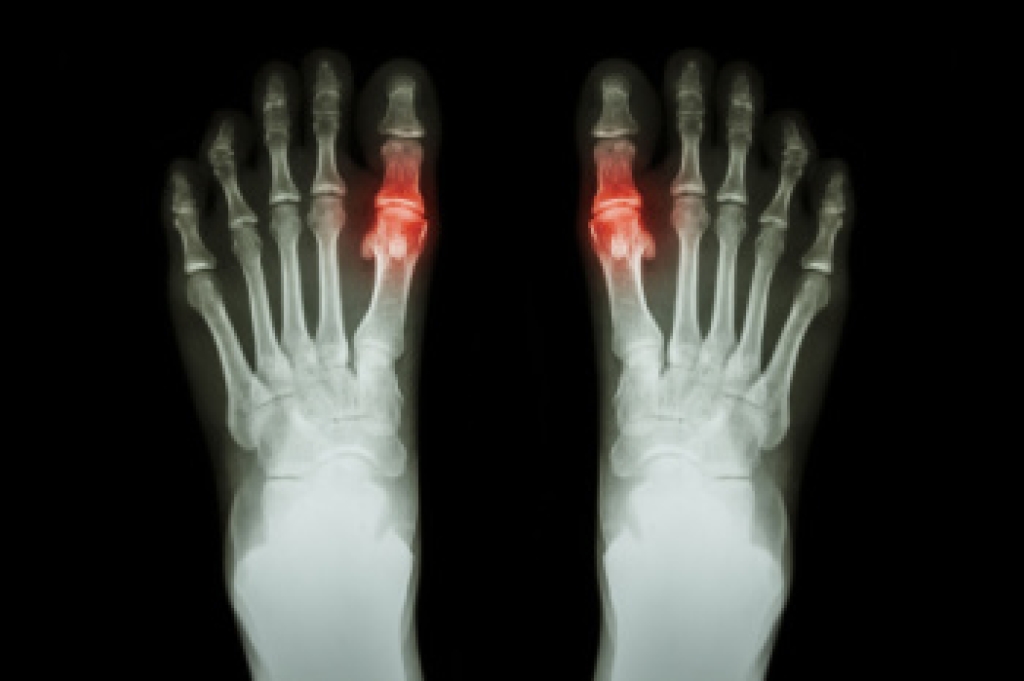

Gout is a form of arthritis resulting in severe pain that can happen suddenly, along with swelling, and tenderness in joints, and often starts with the big toe. This condition occurs when urate crystals accumulate in the joints due to high levels of uric acid in the blood. The pain typically peaks within a few hours and can be accompanied by warmth and redness around the affected joint. Gout attacks can occur suddenly, often waking individuals from sleep with intense discomfort. Recurrent gout episodes can lead to joint damage and deformities, if left untreated. Besides the big toe, gout can affect other joints such as ankles, knees, elbows, wrists, and fingers. Managing gout involves lifestyle changes like reducing purine-rich foods and alcohol consumption, along with medications to lower uric acid levels and prevent future attacks. If you have excruciating pain in your big toe, it is strongly suggested that you consult a podiatrist who can provide an accurate diagnosis and treatment.

Gout is a form of arthritis that is characterized by sudden, severe attacks of pain, redness, and tenderness in the joints. The condition usually affects the joint at the base of the big toe. A gout attack can occur at any random time, such as the middle of the night while you are asleep.